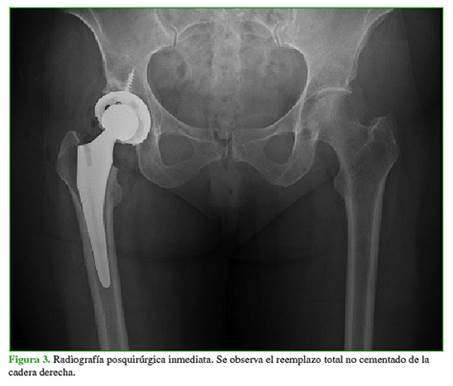

En las radiografías anteroposteriores y de perfil de ambas caderas, se observó un ángulo cervicodiafisario de 131˚, con un índice acetabular y un ángulo centro de borde lateral de Wiberg dentro de los límites normales en ambas caderas. En la cadera derecha, se observaron signos evidentes de desgaste articular con un estrechamiento de la luz articular y esclerosis subcondral, clasificada como grado 2 de Tönnis. Observando con mayor detenimiento, se detectó un escalón articular acetabular a nivel posterosuperior (Figura 1). Se solicitó una resonancia magnética (RM) cuyas imágenes revelaron una zona de hiperintensidad en el área de carga del acetábulo, lo que confirmó la lesión (Figura 2). Los parámetros bioquímicos no mostraron alteraciones significativas.